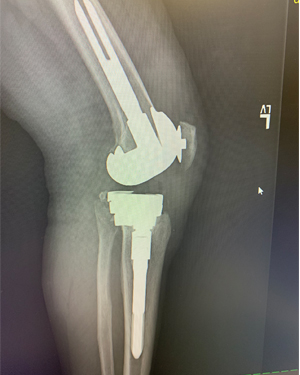

Revision Knee Joint Replacement- Two Weeks after Surgery

Ms. D. Z, is 2 weeks from Right knee replacement and 2 months from Left knee replacement.

This is Ms. D. Z, she is 2 weeks from Right knee replacement and 2 months from Left knee replacement. She is walking well with just a cane at 2 weeks post op.